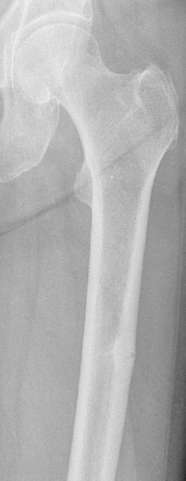

Atypical femoral fractures are rare and atypical thigh-bone fractures that have been associated with anti-osteoporosis medications that inhibit bone breakdown. The causes of these fractures are not yet known. If we can understand what factors lead to the development of these fractures, we can try to prevent them. Nevertheless, the benefits of anti-osteoporosis medications to reduce broken bones due to osteoporosis far outweigh the small risk of an atypical femur fracture.